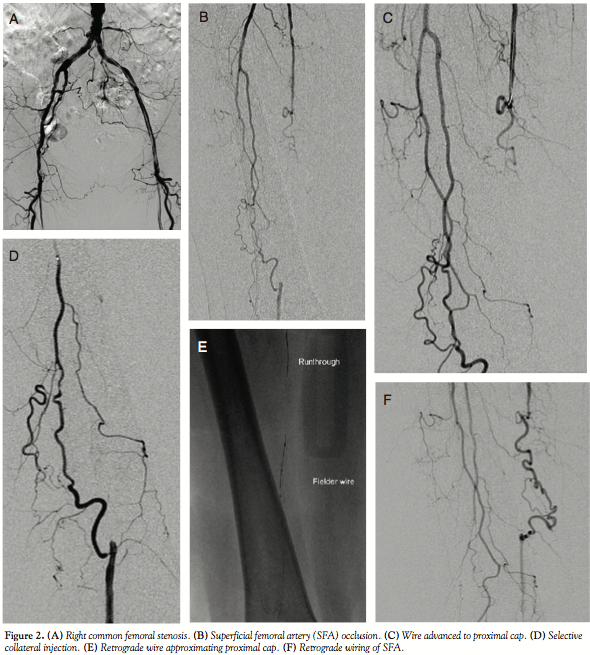

Case 2. An 83-year-old female presented with a history of coronary bypass, left aortofemoral bypass, bilateral carotid endarterectomy, right subclavian bypass, cerebral vascular accident, percutaneous coronary intervention (PCI) of native circumflex, hypertension, hypercholesterolemia, continued tobacco abuse, and claudication. The patient developed an ulceration on the hallux of the right foot and had a known ankle-brachial index of 0.45 on the right lower extremity. Angiography revealed a high-grade stenosis of the right common femoral and occlusion of the SFA (Figures 2A and 2B). She was referred for percutaneous revascularization.

The left groin was accessed with a 4 Fr micropuncture kit (Cook) and upsized to a 5 Fr femoral sheath (Cordis). An Omni catheter was used to cross over to the left side and the sheath was exchanged for a 45 cm, 6 Fr destination sheath (Terumo) placed in the right common femoral artery. Heparin was administered and a Runthrough wire (Terumo) was advanced to the SFA occlusion (Figure 2C). The occlusion involves the take-off of a collateral and there was no “beak” to advance the wire into or for directing a crossing device. Rather than risk a subintimal passage, an additional Runthrough wire was advanced into the profunda with a 0.14˝ QuickCross catheter (Spectranetics). The collateral pathway was engaged (Figure 2D) and the wire was exchanged for a Fielder wire (Abbott). The Fielder, with the support of the QuickCross, was advanced through the collateral into the distal SFA via the retrograde approach (Figure 2E). The wire was then exchanged for an Asahi Confianza wire (Abbott), which was used to wire the SFA in a retrograde manner

(Figure 2F). Given the previous experience from case 1, a 2.0 x 40 Coyote balloon (Boston Scientific) was advanced via the collateral rather than attempting to snare the wire from above (Figure 2G). Following predilation via retrograde approach (Figure 2H), a Runthrough wire was easily advance distally from the antegrade approach (Figure 2I). The vessel was then predilated with a 3.0 x 120 VascTrak balloon (Bard). Intravascular ultrasound (IVUS; Volcano Corporation) was then performed to size the vessel, which was a 4.0 mm vessel with evidence of calcification and diffuse disease. The vessel was dilated with a 4.0 x 150 Coyote at 4 atm for 3 minutes. There was one area of focal calcification that did not yield with balloon inflation; this was addressed with a 3.0 x 20 AngioSculpt (Angioscore) at 22 atm followed by low-pressure inflation with the 4.0 x 150 Coyote.

There was a small dissection noted that was covered with a 5.0 x 40 EverFlex self-expanding stent (EV3) (Figure 2J). IVUS had revealed that the common femoral artery was approximately 6 mm; therefore, balloon dilation was performed with a 6.0 x 20 AngioSculpt. Final IVUS revealed a 5 mm lumen in the CFA with no gradient measured with the sheath; therefore, no stent was placed (Figure 2K). Final angiography revealed good flow to the foot without evidence of embolization or perforation. The left groin was closed with a Mynx closure device. The patient was discharged without incident.